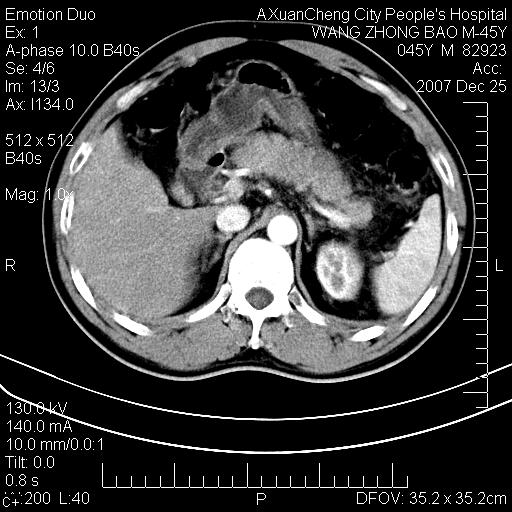

以下是引用qiuleiyu在2007-12-25 18:14:00的发言:[br]胰腺增大,周边渗出改变,肾前筋膜明显增厚,示少量积液.胆囊壁毛糙,周边少许渗出,胆总管壁厚,异常强化,然扩张不明显.结合病程急短;考虑;胆管炎,胆囊炎,胆源性胰腺炎可能大,请结合实验室检查及随访.

以下是引用lisihao在2007-12-25 14:23:00的发言:[br]急性水肿型胰腺炎[br]依据:1、胰腺弥漫性肿大,边缘稍毛糙;[br] 2、双侧肾周筋膜增厚,尤以左侧为甚(重要征象)[br] 3、双侧后胸膜增厚(刺激性炎症);[br] 4、结合病史,查血尿淀粉酶应该可以确诊。